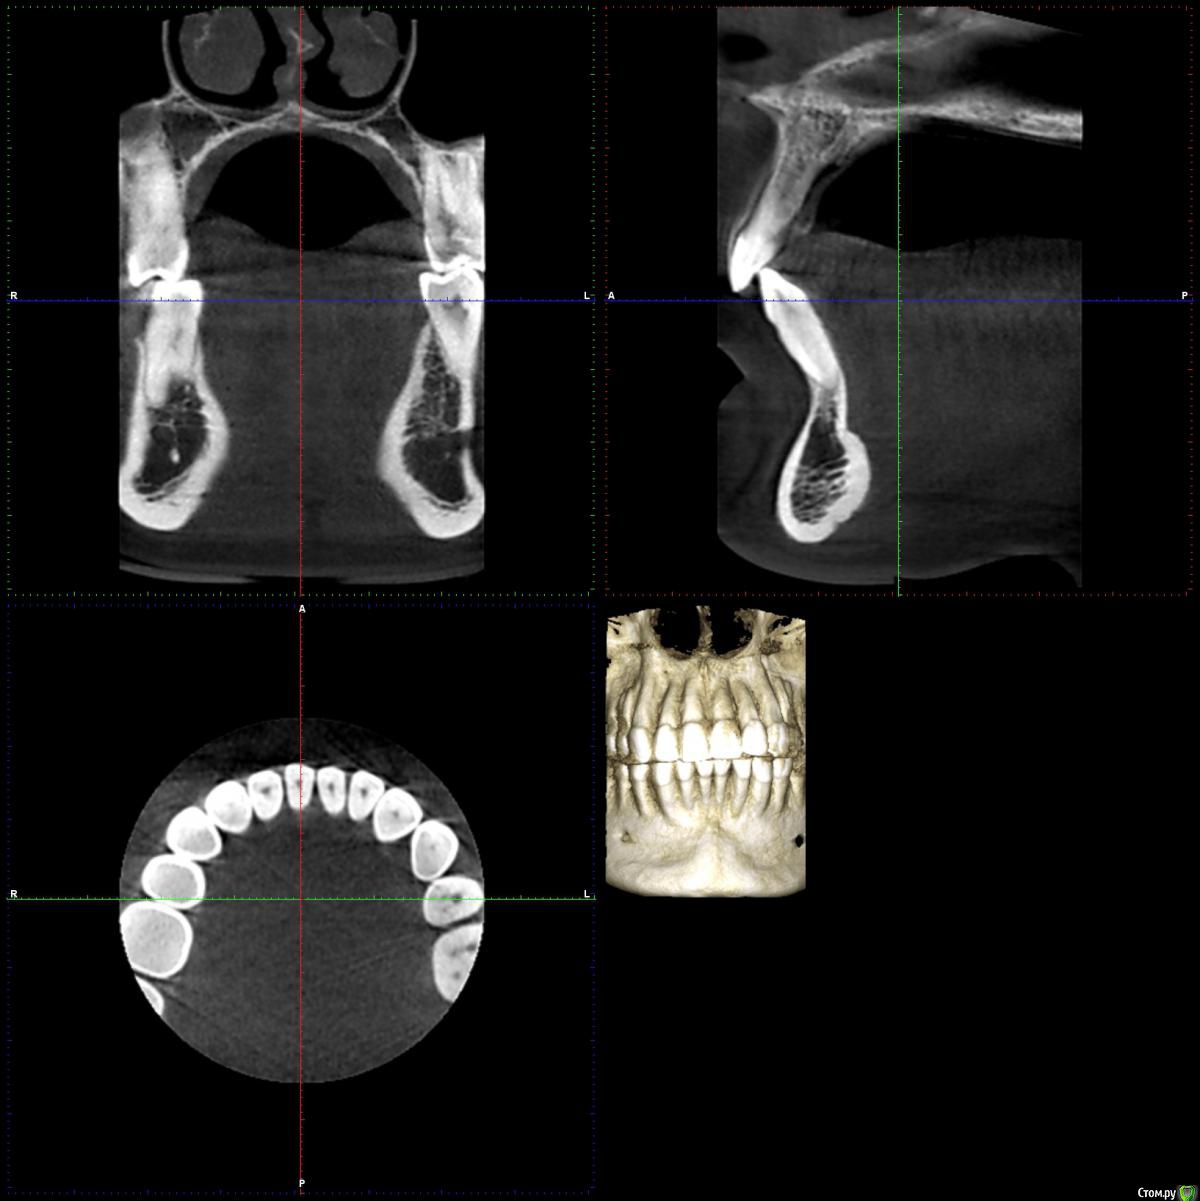

chuvashova_mv Опубликовано 18 июня, 2016 Поделиться Опубликовано 18 июня, 2016 (изменено) Мне 31 год. Тюмень. Сильное оголение корней каждого зуба. Сосочки на месте. Карманов нет. Тонкий биотип десны. Была у неск.ортодонтов, дело не в прикусе.Эндокринолог значит.отклонений не видит (щитовидка в норме, сах.диабета нет, менстр.регулярная сейчас, раньше были сбои), только имт 16,5. Есть ребёнок 3 года, заберем. сама.Гастроэнтеролог - хр.гастродуоденит со школы, желудок работает не в полную меру.Неврология - всд по гипотония.типу., бруксизма нет.Очень сух.кожа с рождения, особенно тяжко зимой.Прилагаются кт и оптг.Вопрос: все очень плохо? У нас в городе вызвались только два врача оперировать, но таких случаев как у меня у них не было.Нужна помощь пародонтологов-хирургов, кто с таким сталкивался. Изменено 18 июня, 2016 пользователем chuvashova_mv Ссылка на комментарий

faity Опубликовано 20 июня, 2016 Поделиться Опубликовано 20 июня, 2016 Судя по ОПТГ дисфункция и деформация ВНЧС, гипертрофия жевательной мускулатуры слева.По фото множественные рецессии и патологическая стираемость зубов.У вас классическая окклюзионная травма которая дала рецессию, стираемость, щелчки в суставе(если уже появились). Вам гнатолог нужен для начала ибо у вас причину сложнее устранить чем последствия в виде стираемости и рецессий.Зубы сжимаете во сне или во время бодроствования? 2 Ссылка на комментарий